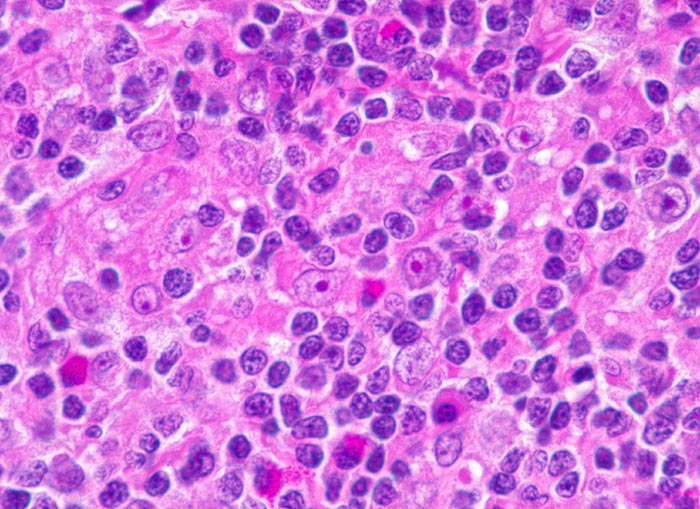

Hodgkin-Lymphom, Mischzelltyp: Hodgkin Zellen

Nachweis von Hodgkin-Zellen: grosse, blastoide Zellen mit grossem Kern und grossem eosinophilen Nukleolus. Ansonsten gemischtzelliges Infiltrat aus reaktiven Zellen: Lymphozyten, Histiozyten, Plasmazellen und eosinophilen Granulozyten.

Vergrösserte zervikale und axilläre Lymphknoten, Fieber und Nachtschweiss.